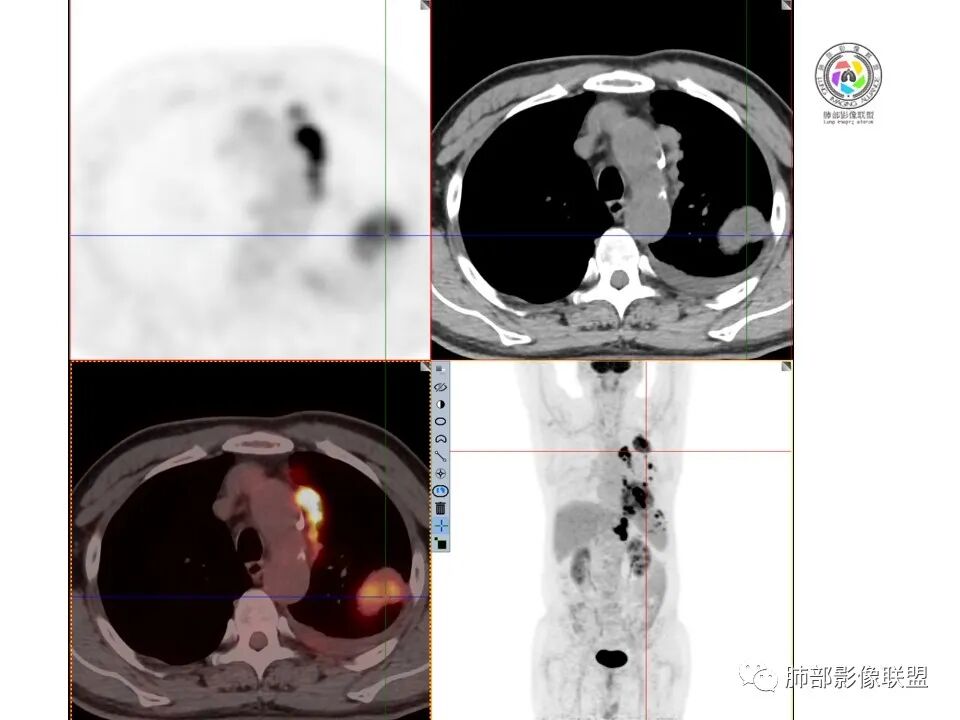

【每日晨读】PET-CT示左侧胸膜区多发高摄取的结节及肿块影,会是罕见病吗?

放射小白: 老年男性,左侧上后胸廓胸膜下团块状占位,左侧膈肌脚可见软组织密度影,纵隔可见淋巴结影,左侧胸腔可见少量积液;左侧胸膜下病变、左侧膈肌病变、纵隔、肺门多发高FDG摄取,首先考虑胸膜间皮瘤,鉴别SFT、转移瘤。

飞鹰行动: 多发病灶,左肺上叶胸膜下,纵膈淋巴结影,部分淋巴结呈串珠状,腰大肌肿胀,SUV值增高,血沉明显增高,考虑炎性病变,结核可能。

秦化君: 左侧胸腔积液伴胸膜局限增厚及多发大小不等结节影,核素浓聚。考虑间皮瘤,鉴别转移瘤。

宇宙: 左上胸膜肿块、左侧胸膜多发结节及左侧膈肌增厚,高摄取,左侧胸腔少量积液,胃窦壁增厚,肝内低密度灶,贫血,考虑转移瘤,鉴别间皮瘤。

丽: 老年男性,左肺上叶胸膜下,纵隔胸膜及左侧脊柱旁见多发软组织密度影,边界光滑清晰,胸膜下脂肪间隙消失,临近骨质无破坏,高摄取,左侧胸腔积液,考虑间皮瘤,鉴别转移瘤

放射线 (王秀仙): 左侧胸膜、纵隔内见多发结节及团块状异常高摄取,左侧胸腔积液,肝内多发类圆形低密度,胸椎左侧异常软组织肿块,考虑转移可能,胸膜间皮瘤?

采莲: 老年男性,有腹疼黑便病史,中度贫血考虑有消化道出血。血象不高,血沉快,低蛋白血症,血肌酐轻度升高,左肺上叶尖后段胸膜肿块,摄取异常增高,纵隔胸膜不规则结节样,摄取也有增高,左侧胸腔积液,胸椎11-12旁长条状软组织肿块,摄取明显升高,胸膜间皮瘤,胸膜结核?鉴别多发转移瘤。不知道腹疼便血原因,有没有肠道肿瘤?

我只是邓较瘦: 左侧胸膜多发多发占位伴胸腔积液,有黑便、胃窦壁有增厚,肝内有多发占位,一元论考虑胃癌并胸膜转移、肝转移?弥漫胸膜间皮瘤?淋巴瘤?

小兜: 左中上腹痛,解黑便,铁蛋白,血沉增高。PET/CT示胸部病灶位于胸膜伴高代谢,不均匀,纵隔5,6区肿大淋巴结伴高代谢。左侧膈肌后方软组织占位,局部突入椎管伴高代谢胆囊颈软组织结节,未见异常高代谢。左侧胸腔积液,首先考虑恶性,PNET?转移瘤?

谢加平: 老年男性,慢性左中上腹痛,解黑便史,左侧胸膜下,肺外PET-CT见多发高摄取结节及包块影,左侧胸腔少量积液,肝S8低密度结节,无摄取。左侧胸膜下考虑多发转移瘤,全腹部CT平扫及增强明确肠道有无恶性肿瘤原发病此,另左上胸膜下包块穿刺活检。

尘缘: 老年男性,黑便伴腹胀两月,肿标除铁蛋白外,其他都不高,胸膜多发高摄取结节伴胸椎旁结节。诊断常规要考虑恶性,主要有三个可能,1、恶性间皮瘤,以胸膜多发结节改变为主伴胸椎旁转移结节,腹部未见明确高摄取,所以这个可能有。黑便可能只是普通胃或十二指肠溃疡引起,需要胃肠镜明确。2、腹部消化道肿瘤伴胸膜及胸椎转移,有黑便两月伴腹痛,要考虑,但腹部没有高摄取原发灶,肿标不高,所以这个可能小。3、淋巴瘤,胃肠道表现就诊,但胃肠道无相关高摄取,肝脾也无明显肿大,无发热,可能不大。除了恶性外,还必须考虑:髓外造血,理由:患者便血二月,贫血明显,椎旁与胸膜旁多发结节摄取一致。疑惑的是髓外造血是否可以这样高摄取?综上:考虑恶性间皮瘤>髓外造血>转移。

空格: 腹痛黑便2周,大概率结肠有问题,胸膜增厚、肺结节、胸水、椎体破坏,明显是个转移灶,原发是胸膜还是腹部, 或者腹部肺部都是一个系统性疾病,比如淋巴瘤。  思路是:1 肠镜必须做,查清黑便原因,有结肠肿瘤,拿一元论肺部转移。   2 肠道没有肿瘤,黑便只是溃疡,  鉴于所有的淋巴结都是膈脚以上,胸膜间皮瘤也是有可能的。

段建民: 患者老年男性,消化道出血来住院,胸部CT提示双侧胸膜多发结节,PET-CT提示高摄取状态,定位胸膜上,胸膜的纵隔侧和胸壁侧及食管旁的淋巴结均有高代谢,肺内未见明显肿块和占位的表现。考虑淋巴瘤?间皮瘤?